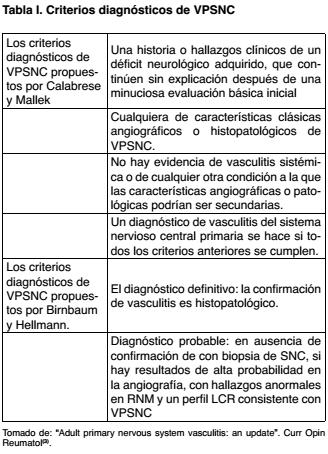

Los primeros criterios diagnósticos de VPSNC fueron propuestos por Calabrese y Mallek en 1988(10). Estos criterios incluyen cambios angiográficos que indican una alta probabilidad de vasculitis, como son: áreas de estrechez vascular, alternando con dilataciones aneurismáticas, en ausencia de compromiso aterosclerótico significativo. Sintomatología neurológica inespecífica y características histopatológicas compatibles con VPSNC realizado por biopsia, en ausencia de elementos que sugieran vasculitis secundaria o de compromiso sistémico. Realizándose el diagnóstico de VPSNC si todos los anteriores se cumplen (Tabla I).

Recientemente, se proponen nuevos criterios en base a los grados de certeza del diagnóstico(3). Estableciendo el diagnóstico definitivo con histología positiva y diagnóstico probable en ausencia de ella, pero con hallazgos en la angiografía, RM y alteraciones en el LCR asociados con un cuadro clínico compatible con VPSNC (Tabla I). Varios estudios han reportado una sensibilidad de la RM para VPSNC cerca de 100%(1,11). En nuestros pacientes todos presentaron alteraciones inespecíficas y variables en la misma, como el compromiso de múltiples estructuras encefálicas en diferentes territorios vasculares, lesiones hiperintensas en T2 y FLAIR, con realce con el contraste a nivel de leptomeninges como se ve en los Casos 1 y 3. Las alteraciones en el LCR, un hecho casi constante en estos pacientes se caracterizan por la presencia de hiperproteinorraquia evidenciada en los tres casos, no presentando alteración del recuento celular ni en los niveles de glucosa (Tablas II y III).